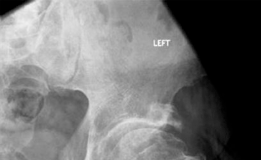

The patient was transferred to the Post-Anesthesia Care Unit in stable condition. Postoperative radiographs confirmed excellent component positioning, with the femoral component in slight valgus relative to the femoral neck, no evidence of notching, and the acetabular component seated with appropriate inclination and anteversion.

Image